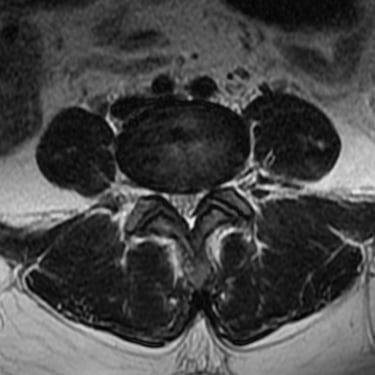

La hernia de disco lumbar se produce cuando el núcleo pulposo del disco intervertebral se desplaza y comprime las raíces nerviosas, generando dolor lumbar, ciática y debilidad en las piernas. El diagnóstico por resonancia magnética (RMN) es el método más preciso para identificar el nivel afectado y el grado de compresión nerviosa. Este estudio permite evaluar la morfología del disco, el canal vertebral y las estructuras adyacentes, orientando el tratamiento médico o quirúrgico. La detección temprana mediante RMN es fundamental para prevenir daño neurológico y planificar una intervención segura y efectiva en caso necesario.